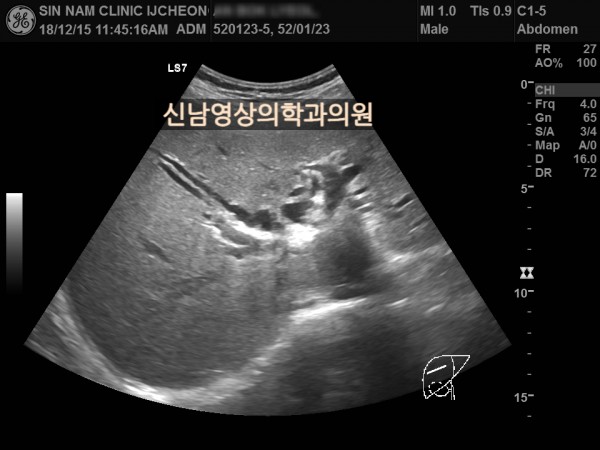

상복부 초음파 적용 사례

본 환자분은 50대 중반의 남성분으로 손가락안이 가렵다는 느낌으로 내원하셨습니다.